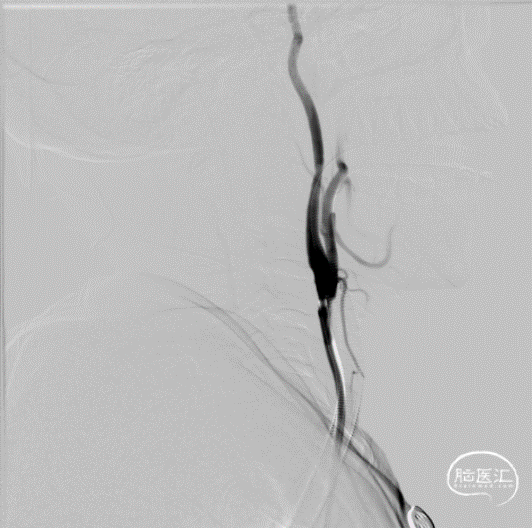

左侧颈内动脉起始段采用中间导管抽吸方法取栓,造影后再通良好。

针对左侧大脑中动脉M1段闭塞采取支架取栓方式。微导管在微导丝引导下通过闭塞段,置于左侧大脑中动脉M2段,撤出微导丝,造影证实真腔。

输送4x30mm Syphonet®取栓支架,支架推送性能良好。利用支架头端的锚定效果缓慢释放取栓支架,可见Syphonet®取栓支架通体显影。支架释放后造影,血流部分恢复。

等待五分钟使支架与血栓充分融合后回撤Syphonet®取栓支架,即刻造影,mTICI ⅡB级。

术后造影确认血流部分恢复,mTICI ⅡB级,结束手术。